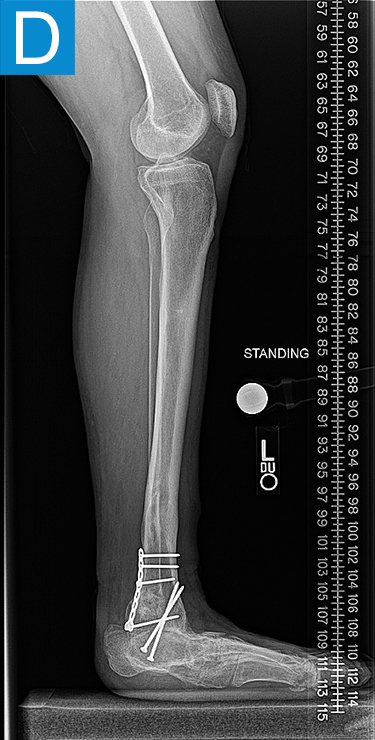

Examination (Figure 1) was notable for a valgus left foot and ankle, with reduced muscle bulk versus the right. His gait was antalgic on the left with minimal knee flexion throughout and no ankle push off (Video 1). Radiographs showed the left leg to be 4 cm shorter than right, with genu valgum, malunion of the lengthened tibia, the recently placed distal tibia fixation, and a ball and socket ankle with short fibula featuring nonunion and malunion at different locations, characteristic of fibular deficiency. He was counseled that a pain-free limb could be provided via reconstructions including hardware removal, distal tibia osteotomy, hindfoot fusion, distal femur osteotomy, and lengthening. He wanted a faster option for painless, high-demand function and asked if he could have tibial osseointegration instead. This was indeed a reasonable option for him. He elected to defer distal femur osteotomy unless the knee remained symptomatic.

Figure 1. Preoperative clinical photos and radiographs. (A) Front and (B) rear views of the patient show a short left leg with foot and ankle valgus and genu valgum and a left calf with reduced musculature. (C) Standing coronal and (D) lateral tibia radiographs depict the prior distal tibia lengthening with fibula nonunion, ankle fracture with fixation, ball and socket ankle, and short fibula. Also note the genu valgum.